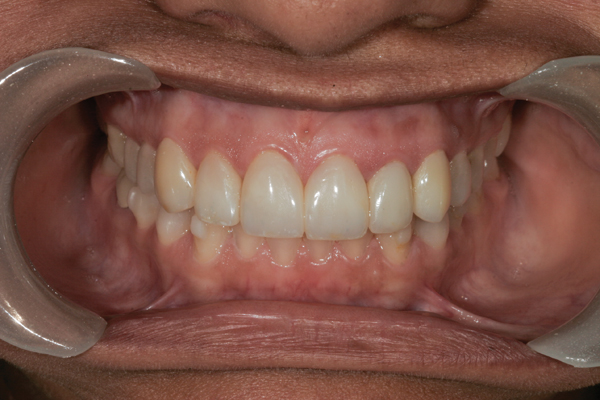

Intraoral Camera

The Intraoral Camera

The intraoral camera is an excellent visual tool that allows the patient to see exactly what the dentist sees in their mouths. They say a picture is worth a thousand words and this revolutionary diagnostic dental instrument eliminates any confusion between doctor and patient when communicating treatment options. Capturing images with the intraoral camera is painless and there is no radiation exposure risk as visible light is used to generate the photographs.